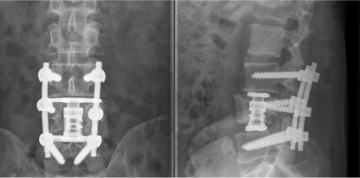

Eine dorsale Instrumentierung, also eine Versteifung von Wirbelsäulenabschnitten von hinten, ist erforderlich, wenn komplexe oder instabile Wirbelkörperbrüche vorliegen. Diese Methode wird sowohl zur endgültigen Stabilisierung eines Bruchs als auch als erste Maßnahme bei instabilen Wirbelbrüchen eingesetzt, oft in Form einer Notfalloperation.

Bei dieser Technik werden in die Wirbelkörper ober- und unterhalb des gebrochenen Wirbels jeweils zwei Schrauben (links und rechts) von hinten eingebracht und durch ein Stabsystem miteinander verbunden. Dadurch wird die Belastung des gebrochenen Wirbels überbrückt, was dessen Heilung ermöglicht. Die Operation kann entweder konventionell „offen“ mit einem großen Hautschnitt oder minimalinvasiv mit mehreren kleinen Hautschnitten durchgeführt werden.

Hintere Stabilisierung eines Bruches des 12. Brustwirbelkörpers mit zementierten Schrauben und in minimalinvasiver Technik bei Osteoporose.